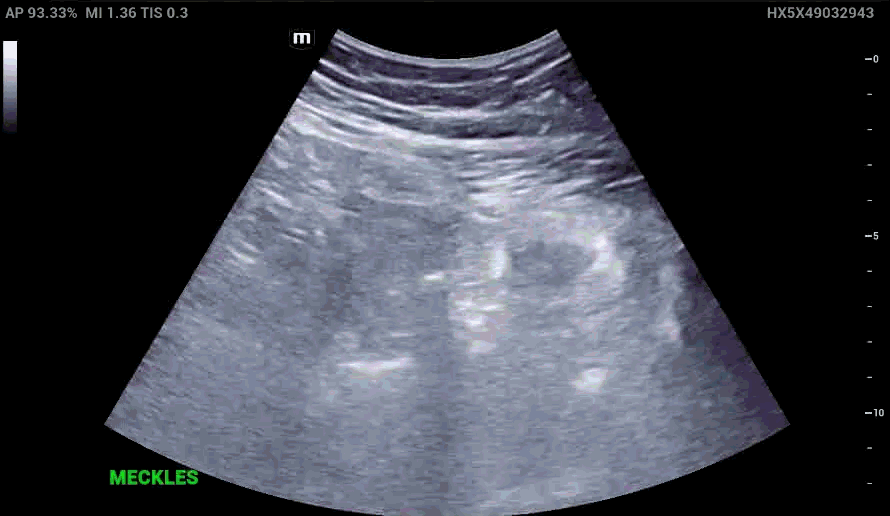

RLQ US:

Appendcitis was high on the differential with what looked like an appendocolith in the right lower quadrant with posterior acoustic shadowing. CT was ordered which showed the following:

The characteristic features of inflamed Meckel’s diverticulum can include the following findings:

• Fixed, blind ending tubular or cystic structure in the bowels.

• Thickened wall

• Irregular mucosal layer

• Tubular hyperechoic structure

• Surrounding hyperechoic fat representing pericolic inflammation

• May contain fluid, air or particulate material

• Hyperemia in the diverticular wall indicating inflammation

• Increased vascularity in the surrounding hyperechoic layer, which suggests perforation

• Small bowel obstruction may be present as a complication